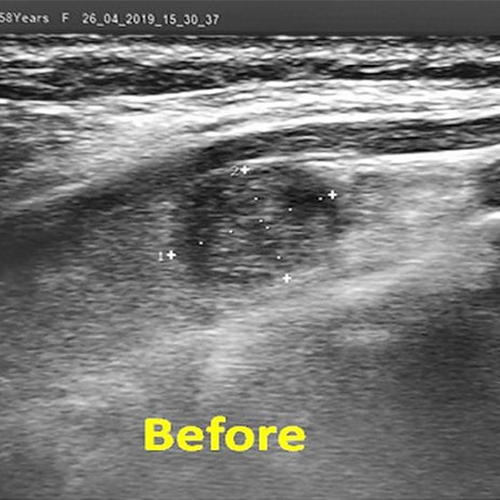

We performed thyroid embolization treatment in our 58-year-old patient with a 12cm giant nodule extending into the chest cavity causing severe dyspnea. A year later, the nodule shrank by 85%, the neck of the patient got slimmer, and shortness of breath disappeared completely. In addition, the mild hyperthyroidism previously present in the patient improved and the thyroid hormones returned to normal.